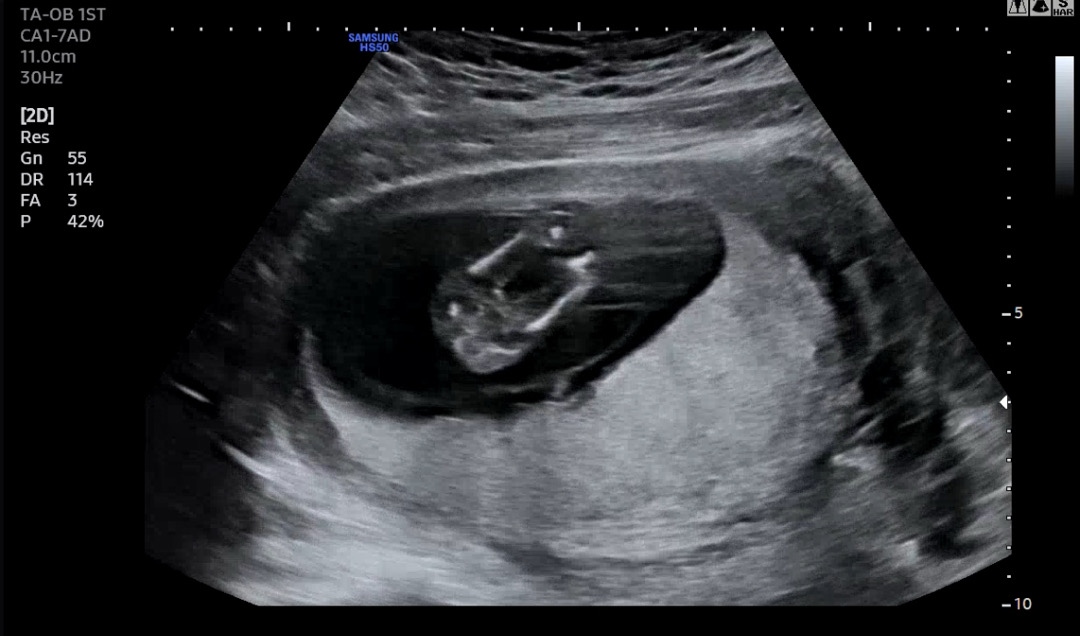

14주0일차 함께봐주세요! 부탁드립니다!

14주차 0일차 정확하지 않더라도 바뀔 가능성이 있더라도, 딸인지 아들인지 너무 궁금합니다! 봐주실 수 있을까요? ㅎㅎ

딸처럼보여요!

여아 같아요~!